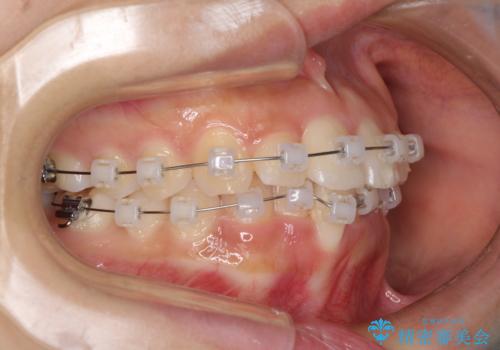

- クリアブラケット

- 治療期間

- 9ヶ月

- 治療回数

- 5-10回